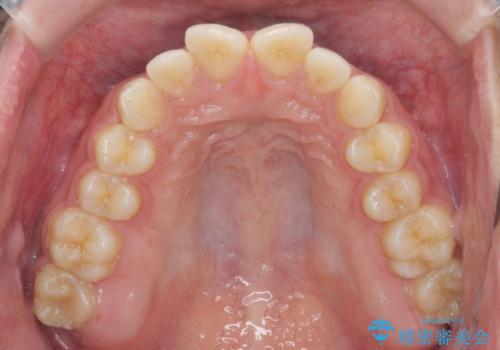

- 出っ歯のように見える前歯の角度を治したい、と矯正治療を希望され来院されました。

抜歯をせずにマウスピース矯正システムインビザラインを用いてしっかりと前歯の角度を改善していきます。

前歯の角度だけでなく内側に倒れ込んでいた奥歯もしっかり起こすことで咬合関係も理想的に仕上げています。